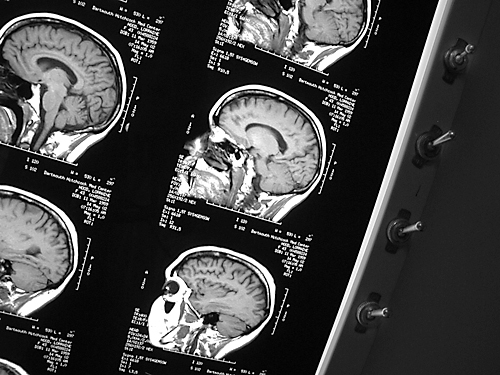

MRA